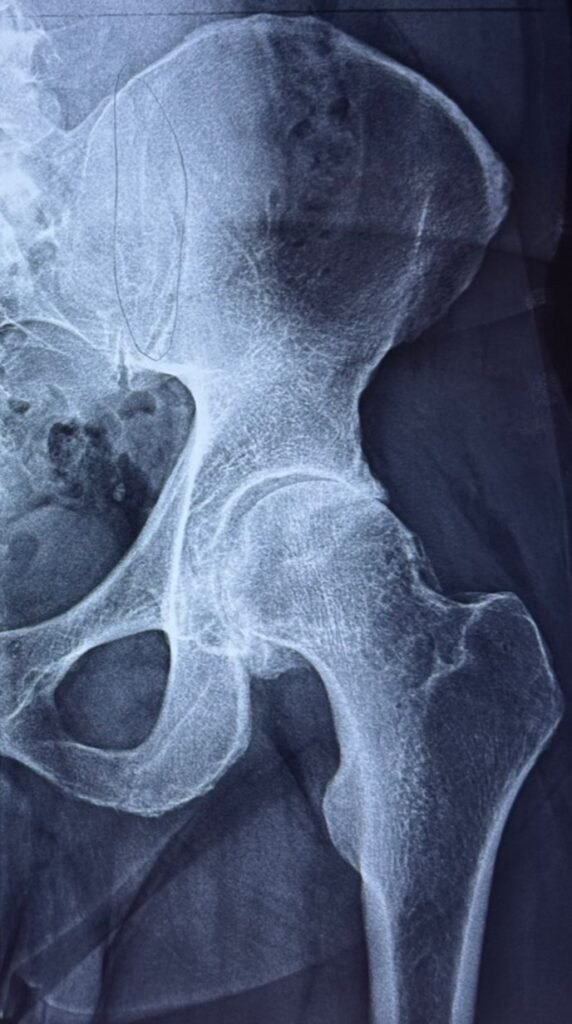

El desgaste de cartílago o artrosis, en cadera se llama “coxartrosis”. Existe muhcas causas como una extremidad mas corta que la otra, pinzamiento fémoro-acetabular, necrosis avascular.

La coxartrosis da dolor en la INGLE, puede limitar el movimiento para sentarse, manejar un vehículo, o hacer ejercicio.

La prótesis de cadera es un conjunto de piezas:

-Copa

-Inserto

-Cabeza

-Vástago

Juntas reemplazan la articulación original, devolviendo su función, idealmente sin dolor.